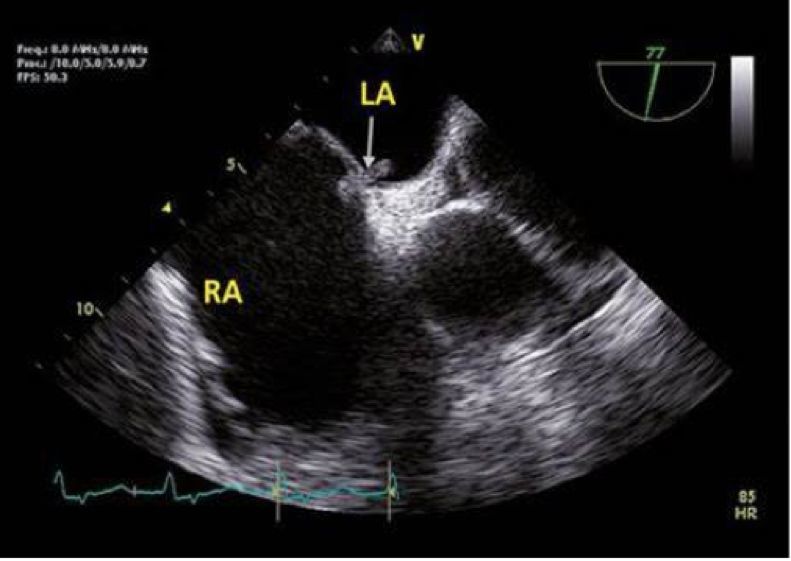

列位看官,你们肯定忽视了一种心脏疾病所致的偏头痛:卵圆孔未闭。

卵圆孔其实是心房原发隔与继发隔之间的一个缝隙。由于这个解剖结构的存在,当情绪激动等其他原因导致胸腔内压力过高时,可能会导致心房之间出现右向左的分流。因静脉血中化学物质如 5-羟色胺等血管活性物质较多,在分流后会导致脑血管扩张出现偏头痛。

所以在临床中会有一些不明原因偏头痛的患者,能够卵圆孔未闭封堵中获益。

卵圆孔未闭,一般是左向右分流,在右心压力升高时,可出现右向左分流